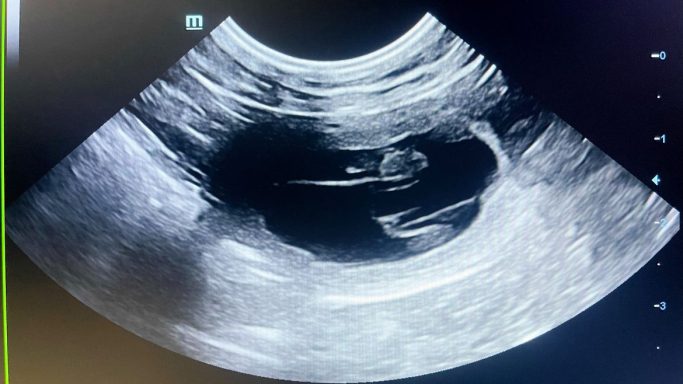

Ultraschall

Am 24. Tag nach der Bedeckung mit Anderl, waren wir beim Ultraschall mit Peppa um zu kontrollieren ob sie tragend ist und mit den Welpen alles in Ordnung zu sein scheint. Wir haben definitiv eine Trächtigkeit von Peppa gesehen und bereits Herzschläge gehört. Wieviele es werden ? Bleibt noch ein Rätsel bis zum Röntgen... noch ist sie schön schlank und sportlich...